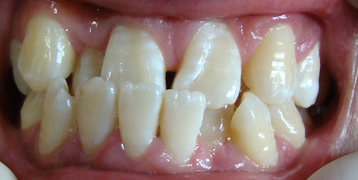

牙齿错位畸牙往往牵拉牙槽骨和颌骨引起脸

型改变。青春期面部骨架尚未定型,因此及

时矫治牙齿,牵引牙槽骨移动,从而使脸型

得以改变。

牙齿错位畸形多因牙齿拥挤,传统的正畸医生

要通过拔牙来缓冲牙齿间隙,据统计拔牙率高

达40%,但穗华隐形技术可以使拔牙率控制在

5%以下,独领国内矫正领域。